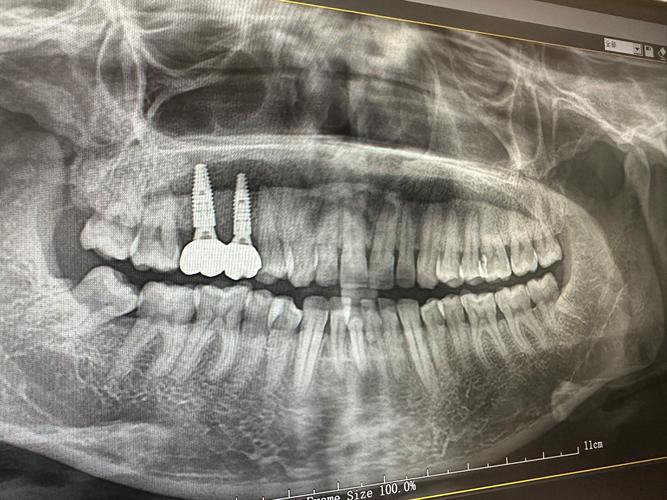

正畸治疗依赖牙槽骨的改建能力:牙齿移动时,牙槽骨一侧吸收、一侧增生,若骨量不足,吸收速度可能超过增生速度,导致牙根暴露、牙齿松动,甚至骨开裂,对于中重度牙槽骨薄患者,正畸前需通过CBCT等影像学评估骨量,判断是否需要植骨,轻度骨薄可通过轻力移动、延长矫正周期等策略调整,但中重度骨薄(如骨厚度<1mm)则需植骨增加骨量,为牙齿移动提供足够支持。